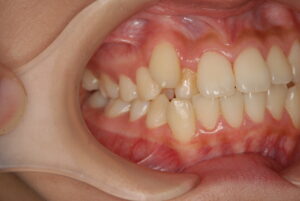

実際の症例紹介(20代女性/裏側ワイヤー矯正)

治療前

治療後

・主訴:八重歯と前歯の突出

・治療法:裏側からのワイヤー矯正(リンガル)

・治療期間:約1年半〜2年(目安)

・予想される副作用・リスク:装置装着後の違和感・疼痛、発音のしづらさ、一時的な咀嚼効率低下、ブラッシング不良によるむし歯・歯周病リスク など

※写真は代表的な症例です。口腔内の状態により治療法や期間は異なります。詳細は初診相談でご説明します。